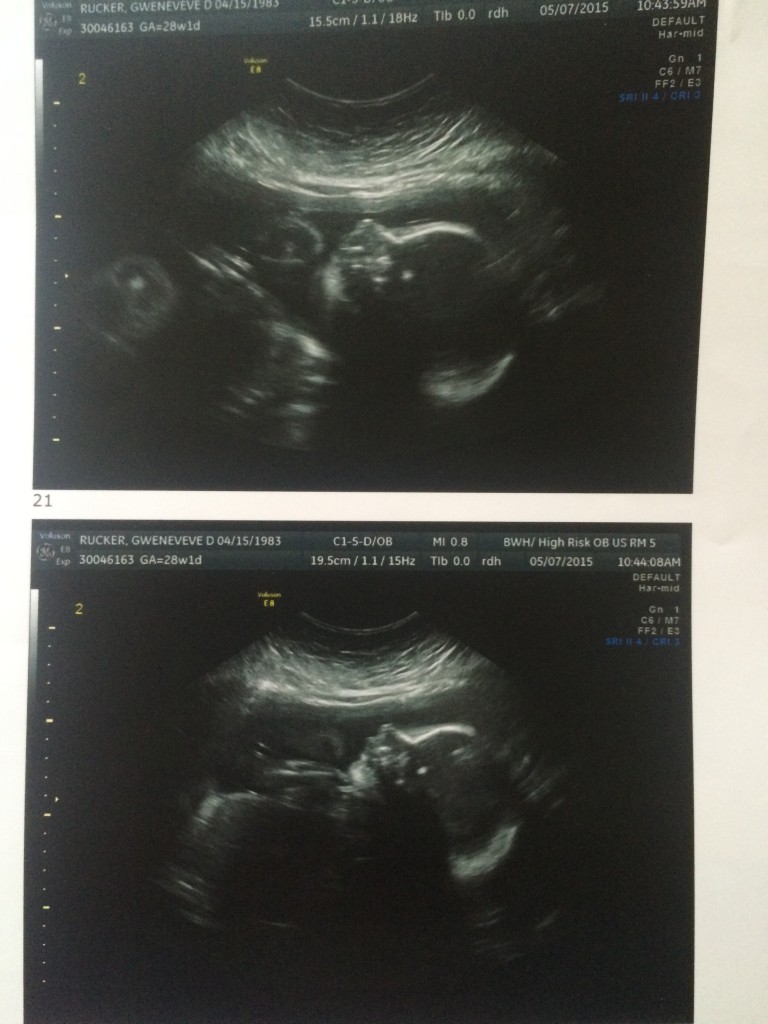

Things are moving along rapidly! Gwen and the boys are continuing to do well, though Gwen has been getting steadily less comfortable as William and James get larger. We are now up to no less than 3 doctors visits a week, with non-stress heart checks on Mondays and Fridays and trips down to Boston for ultrasounds and OB/GYN visits. Suffice to say, we are staying busy! The plan remains for Gwen to be induced during the first week of July, though we have not nailed down the exact day just yet. In the mean time, I’ve been working on trying to help Gwen stay caught up with the housework, and complete a few projects that will help prepare for the boys’ arrival. We are getting close! I can hardly wait.